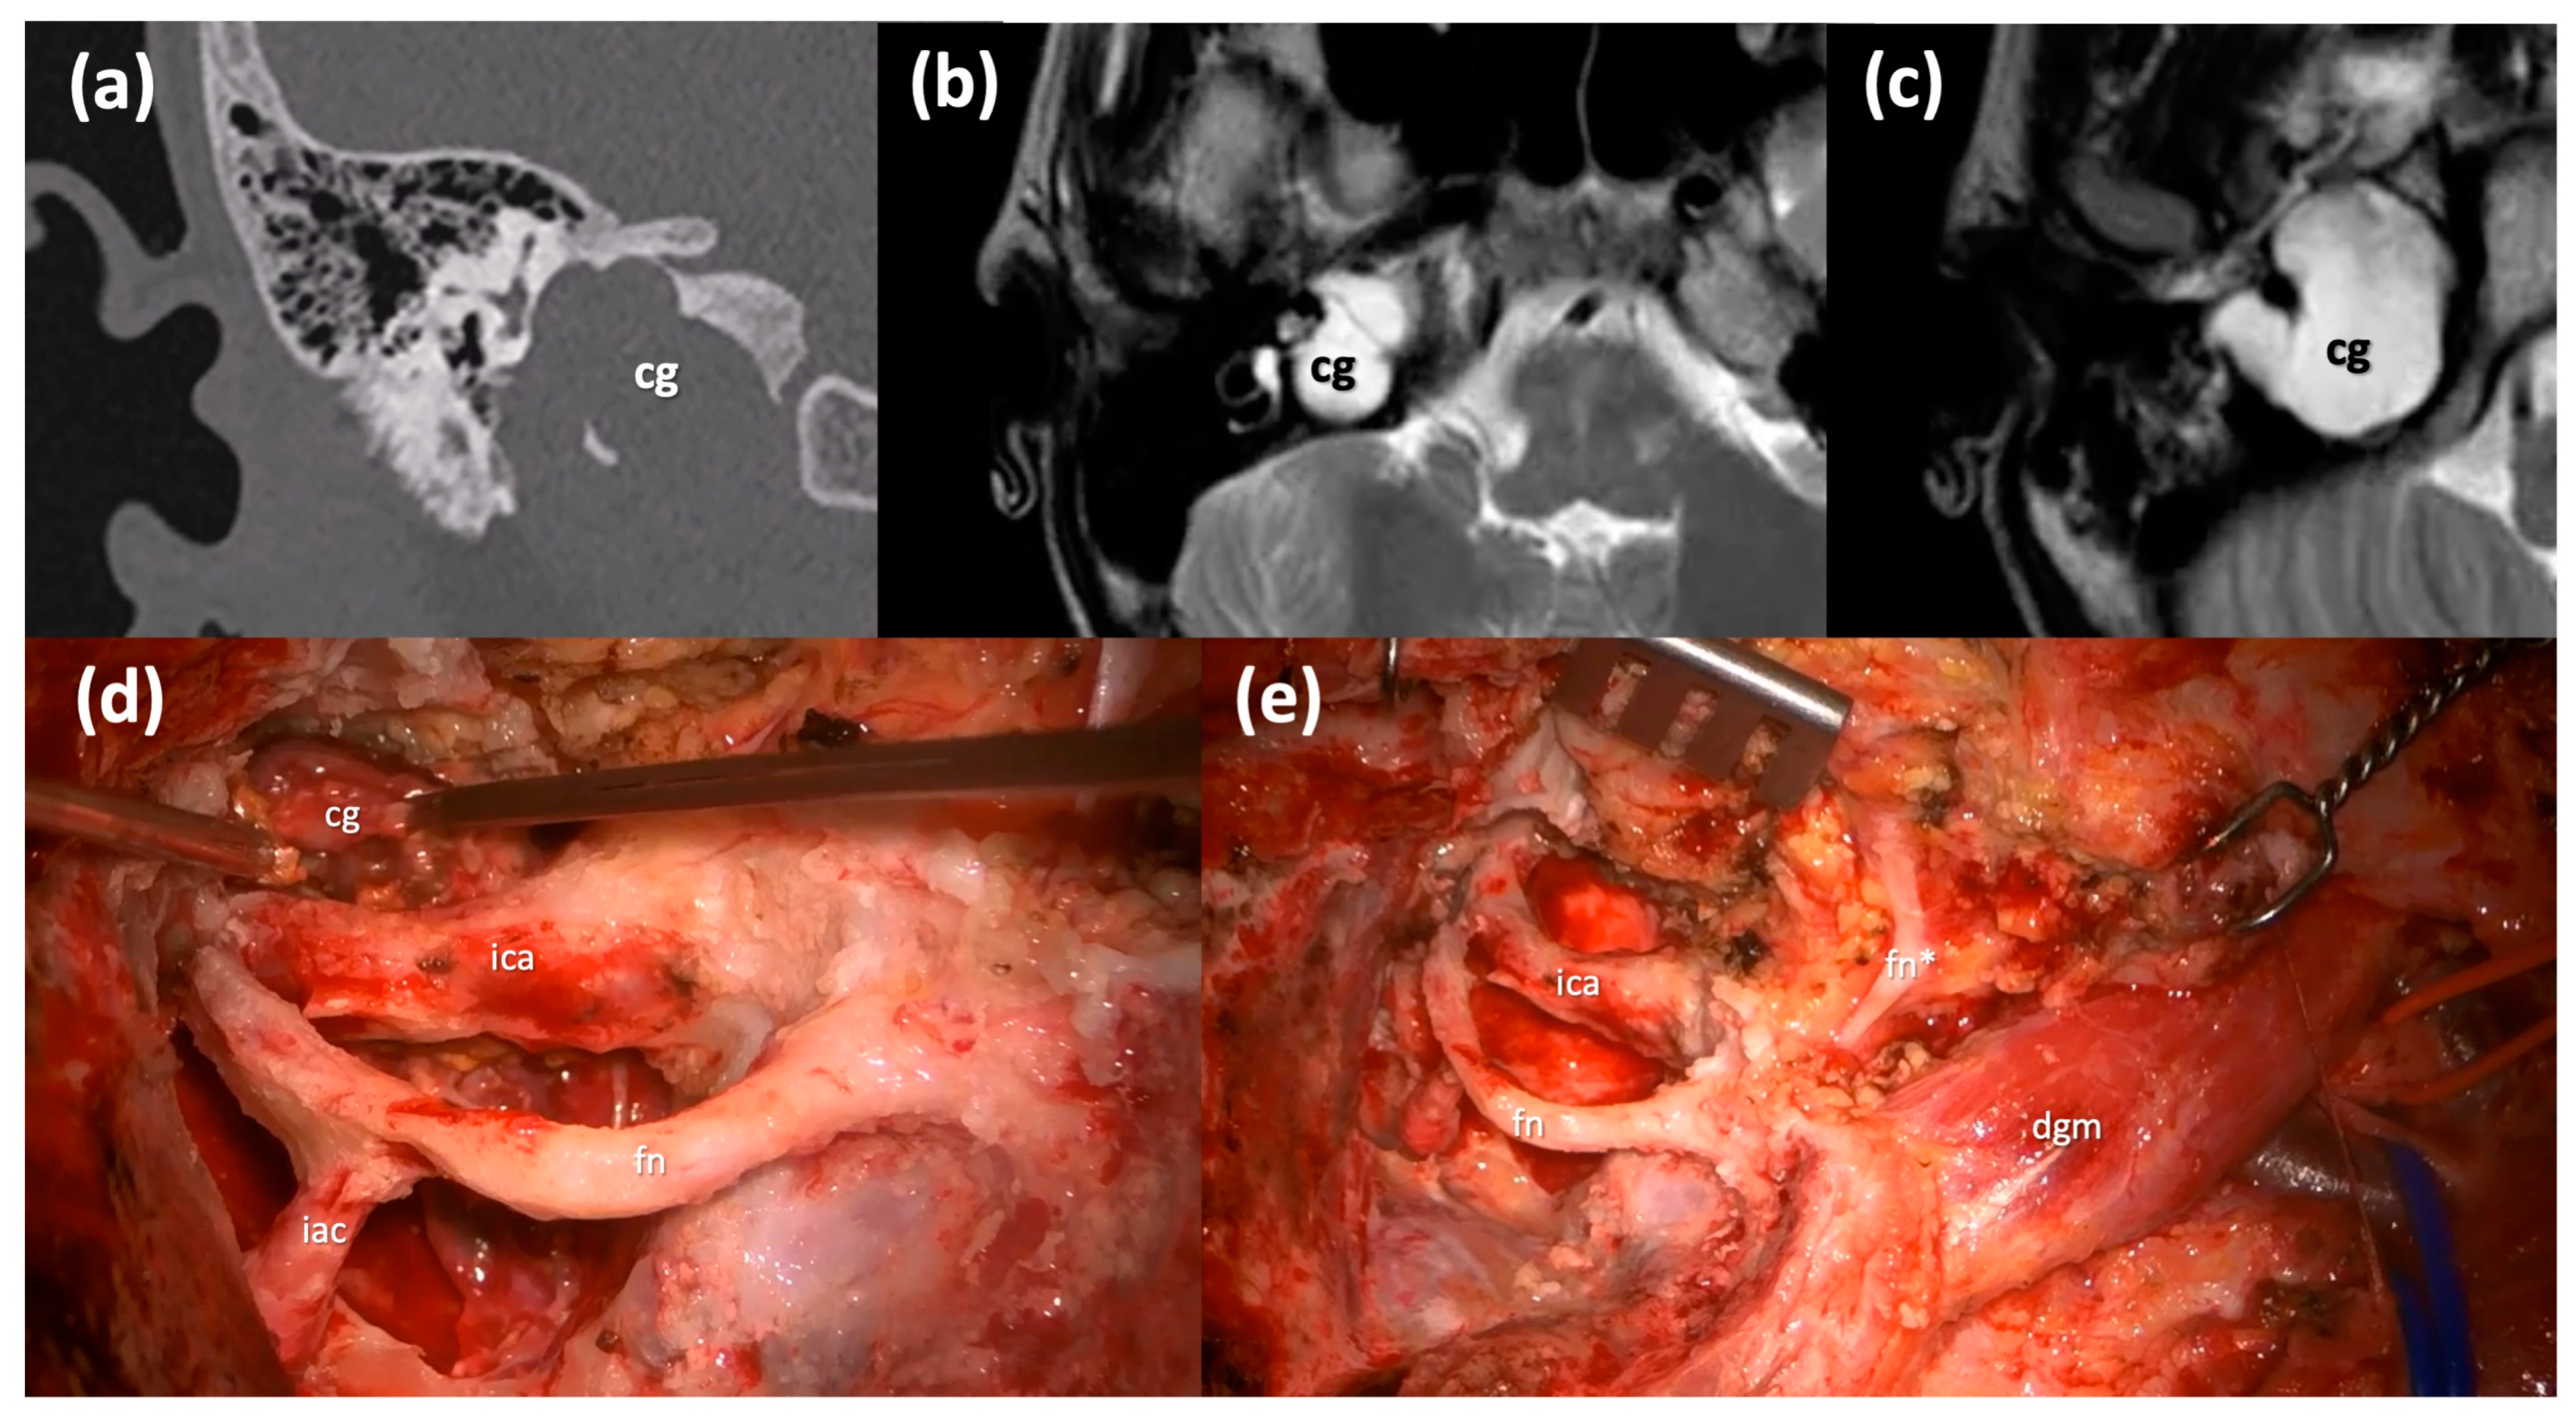

The Type B infratemporal fossa route in combination with a transotic one is selected in case of a pre-operative severe-profound sensorineural hearing impairment since it sacrifices the hearing function, and it requires the blind closure of the external auditory skin. This technique is based on the skeletonization of the facial nerve, which is kept suspended in its bone canal from the stylomastoid foramen to the fundus of IAC, and on the skeletonization of the intrapetrous ICA in its vertical and horizontal portions. This is possible through the anterior transposition of the mandibular condyle and the middle meningeal artery and the V3 trigeminal branch section, to allow for the control of the horizontal portion of the intrapetrous ICA. This approach allows for the removal of the lesion with its capsule from the petrous apex to the clivus anterior to the ICA (Figure 4), while allowing for a direct visualization and a complete control of the whole intrapetrous ICA. Once the cholesterol granuloma has been removed, the surgical cavity is filled with abdominal fat.

Figure 4.

Type B infratemporal fossa approach combined with a transotic approach. (a) Coronal CT scan of a massive right Type C PACG. (b,c) Axial T2-weighted MRI sections of the same PACG showing its hyperintense signal and its relationship with the IAC, the ICA and the clivus. (d) Surgical step: the facial nerve has been completely skeletonized from the IAC to the stylomastoid foramen and it is left in a bridge-like fashion over the surgical field; careful maneuvers are employed to dethatch the PACG from the horizontal segment of the ICA. (e) Surgical step: final surgical field where the PACG has been completely removed. cg, cholesterol granuloma; ica, internal carotid artery; fn, mastoid segment of the facial nerve; iac, internal auditory canal; fn*, intraparotid facial nerve; dgm, digastric muscle.

This route is suggested if the cholesterol granuloma has a significant extension, and it is closely related to the intrapetrous ICA. In all the cases of intrapetrous ICA involvement, the surgeon must take into account the necessity for a detailed radiological preoperative study of the vessels [8].

An arteriography and a balloon occlusion test of the ICA are crucial in the preoperative study, since an intra-operative injury of the vessel may require its direct closure, thus assessing the presence of a collateral blood circulation is fundamental for the preoperative planning. In our series, we had one case of intrapetrous ICA vertical tract fissuration that we repaired during surgery, and the immediately carried out angiography highlighted a stable pseudoaneurysm that did not require any neuroradiological procedure.